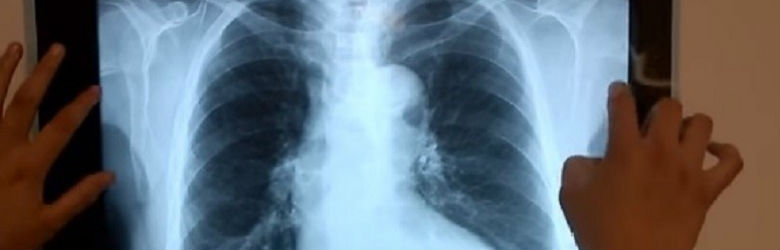

¿no encuentras respuestas a tus preguntas sobre el examen dele b2? Examen de radiología urjc 2013. Dos estructuras de distinta densidad se encuentran en contacto.b. Recuerda la anatomía normal y su representación en las imágenes de radiología, us, tc o rm.